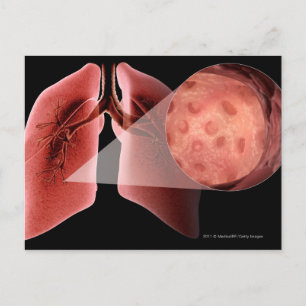

Inflammad luftväg under en astmaattack vykort

Pris21,00 kr